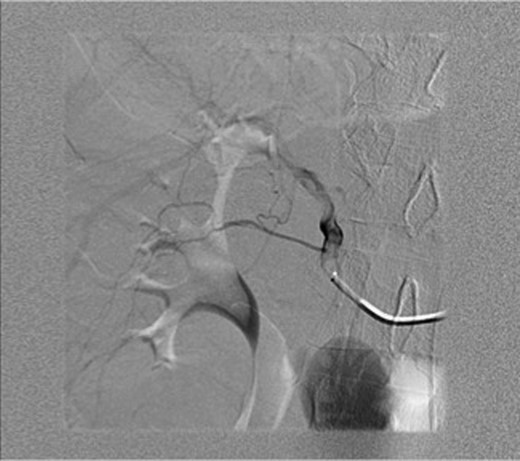

An ultrasound was done showing a mass in the right upper quadrant with no visualization of the gallbladder and no evidence of biliary tree dilatation. Therefore, a CT scan was performed which showed a large haematoma in the gallbladder fossa, which distends the gallbladder wall causing mass effect (Fig. 1a and b). Furthermore, active extravasation of IV contrast was seen. Initially, this was not clear if the haematoma is arising from the liver or within the gallbladder. Given his haemodynamic stability he was taken to the interventional angiography suite for an arteriogram of his abdominal aorta and splanchnic vessels. The bleeding was localized to a branch of the cystic artery and no pseudoaneurysm was identified (Fig. 2). Then, embolization of cystic artery with gelfoam material was performed. Since, embolization of the cystic artery proper was done, the decision was made to explore the patient and perform a cholecystectomy. Prior to the operation the patient became tachycardic at 100 with a systolic blood pressure of 90 and a diastolic of 60. His repeat haemoglobin was 10.1. Appropriate resuscitation with blood transfusion was performed.

Arteriogram of abdominal aorta and splanchnic vessels showing localized bleeding in a branch of the cystic artery and no pseudoaneurysm.